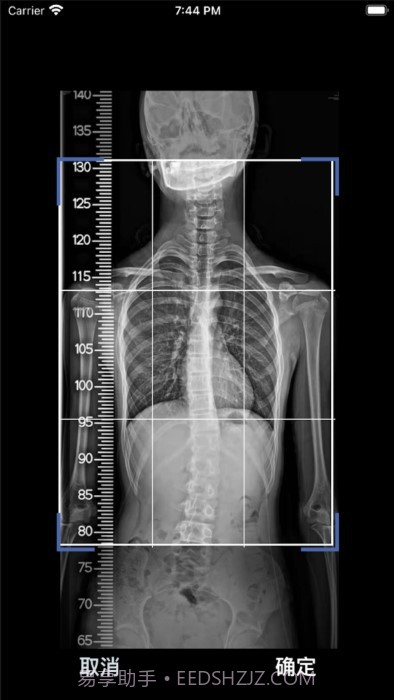

这款cobb角测量分析平台简直大概是医生和脊柱侧弯患者的福音!🌟 通过智能测量功能,能够迅速获取cobb角,准确率高得让人放心。对于有脊柱健康需求的小伙伴们来说,了解自己的状况特别重要,不仅能省时省力,更能随时存储和导出数据,后续分析也大概是轻松搞定!总之,这款应用为提高医疗效率、帮助患者掌握健康状况提供了强有力的支持,真心推荐给大家!

智能测量功能超赞,帮你快速获取cobb角,省时省力!

自动识别和标记椎骨,精准度高达95%,真大概是放心!

应用使用AI自动识别椎骨,确保精确度高达95%,让你用得放心。